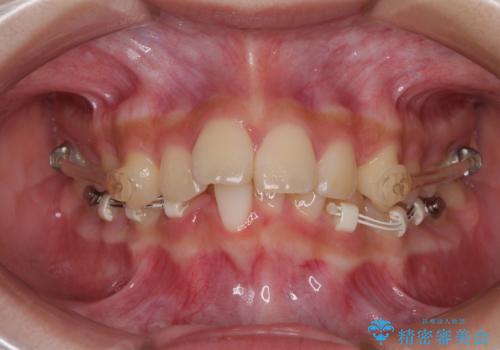

深い咬み合わせを改善するためには、上顎臼歯を後方に移動させつつ、下顎の小臼歯を直立させる必要があります。

インビザライン単体で対応ることも検討できますが、達成する可能性が低いため、カリエールディスタライザーという補助装置を併用して、より確実性を上げることとしました。

奥歯の咬み合わせと深い咬み合わせを改善した後、インビザラインで歯列を整えることとしました。

ワイヤー装置と補助装置を有効に活用し、さらには高校生ということもあり、1年9か月で狙い通りの仕上がりを達成することができました。